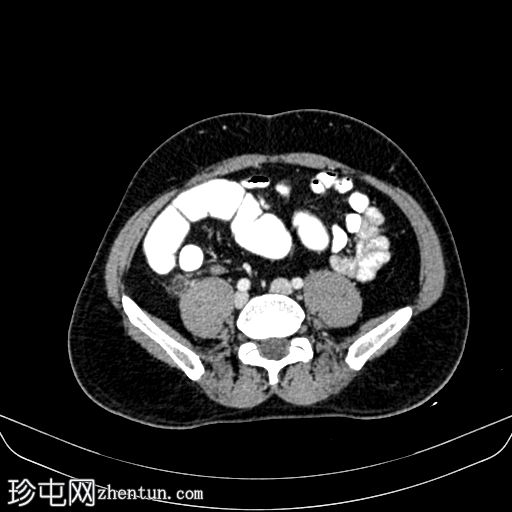

轴位增强扫描

动脉期

平扫CT显示,盲肠后外侧壁旁可见一边界清晰的卵圆形脂肪密度影,周围环绕一薄层高密度环(“高密度环”)。周围脂肪间隙轻度改变,无游离液体,邻近结肠壁未见增厚。动脉期,病灶仍为脂肪密度影,高密度环略有强化;未见动脉出血。